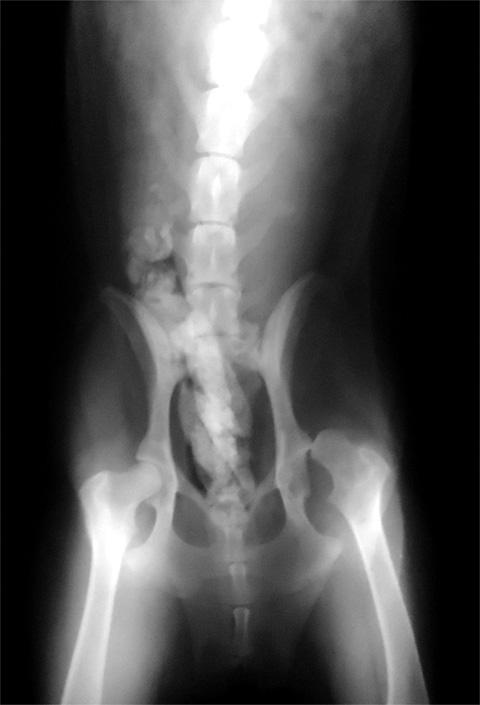

甜甜的X光片拍照

我花了一點時間拍了X光

請看一下目前的嚴重程度?

感謝!

恩恩 另一腿非常的嚴重@_@!!